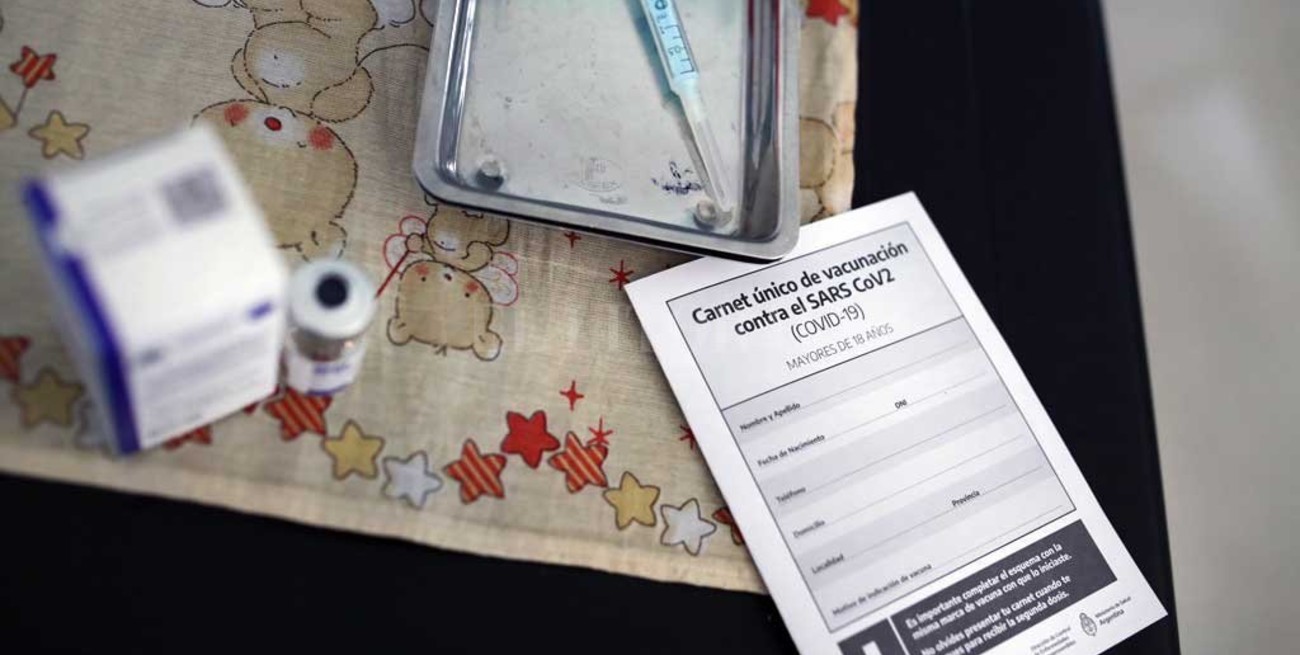

Ya se aplicaron 39.599

Al 5 de enero las jurisdicciones reportaron la aplicación de 39.599 del primer componente de las casi 150.000 dosis distribuidas de la vacuna Sputnik V, según confirmó el Ministerio de Salud de la Nación.